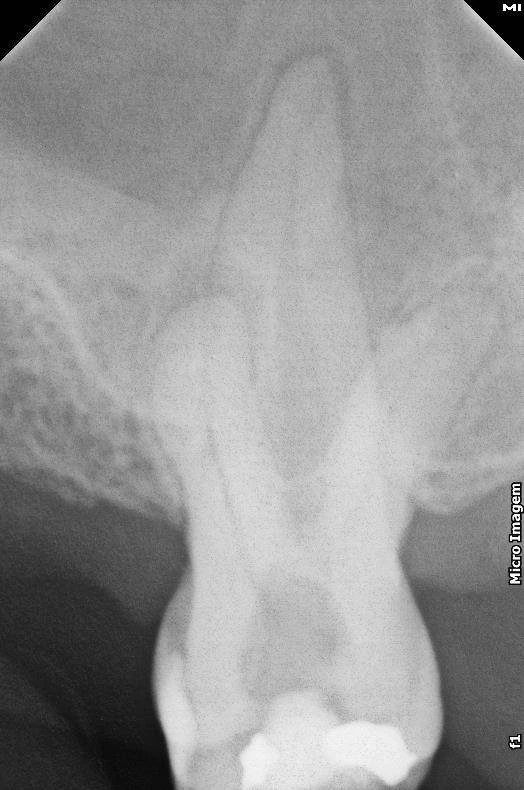

Endodontia (depois)

Endodontia

O que é?

O tratamento endodôntico ocorre geralmente por cárie profunda, infiltrações ou fratura dental que compromete o nervo (a polpa) dos dentes. Quando isso acontece a pessoa sente muita dor. Às vezes a dor é espontânea, pulsátil e intensa. E costuma durar várias horas, sem cessar.

Aqui o tratamento de canal é realizado sem dor e sem trauma. Com técnicas mais modernas de anestesia, instrumentação rotatória, raio-x digital e, quando possível, realizamos os canais em sessão única.

Esse trabalho é realizado pelo especialista em endodontia, Dr. Lucas Ribeiro.